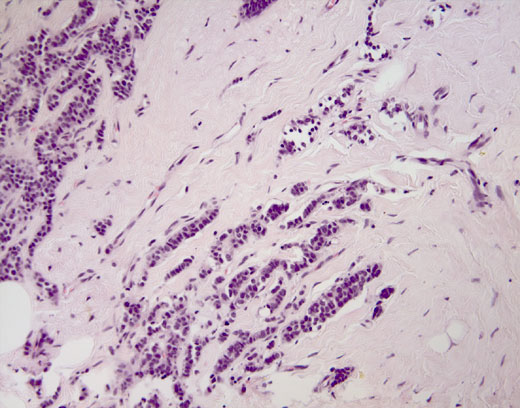

Cross-section #7 - 20X

click on the slide photo to see 40X magnification